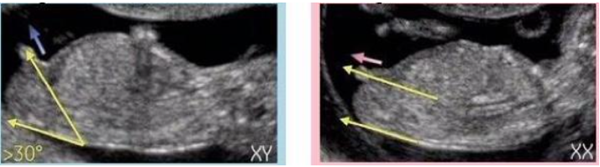

nt检查的时候,医生一般是能看到二维超声的全景图的,也就是宝宝的全身,报告上也有可能会放全身图,NT单子上会有宝宝的图片,可以根据英国的nub点原理来判断男女,nub theory指的是通过NT检查图片上的胎儿特征点和尾椎的角度判断男女的方法,男孩的特征点与身体呈30度角,还多一些,而女孩儿的特征点几乎和躯体平行。还有就是如果是男宝宝,屁股位置会微微上翘,后背脊柱成圆弧状,因为要留空间发育前列腺,相反,女宝宝后背脊柱就相对就平一些。